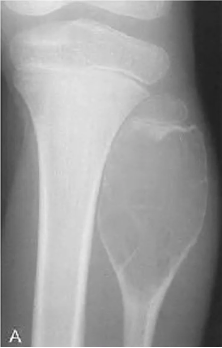

Tumeur à cell géante (ostéoclastome) : 80% bénin 20% Malin

- 20-40 ans

- Prompt à fx patho

- Touche les os longs, subarticulaire, près plateau physe, soap bubble apparence

- « Soap bubble appearance », plusieurs compartiments

- Bien défini, petite zone de transition (bénin)

- Moins bien défini et longue zone de transition (malin)

- Distal radius ++ (malin)

- Risque de tourner en ostéosarcome